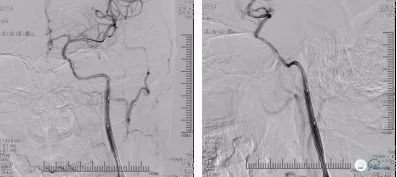

DSA(2018-06-11):右颈内动脉C4-C6段管壁不光滑,多发斑块形成,存在多发串联狭窄;右侧大脑前动脉A1纤细,显影浅淡,右侧大脑中动脉通过软脑膜支向右侧大脑前动脉代偿供血,前交通动脉开放欠佳;左颈内动脉C1段长节段闭塞,局部可见血栓影,左侧颈内动脉C6段以远经眼动脉代偿供血,可见浅淡显影,左侧大脑中动脉、左侧大脑前动脉未见显影;左锁骨下动脉造影可见左侧大脑后动脉通过软脑膜支向左侧大脑中动脉、左侧大脑前动脉代偿供血,左侧后交通未见开放(图5)

在局麻下右股动脉置入8F动脉鞘,沿常规泥鳅导丝携带5F多功能导管、8F球囊导管在路径图下送至左颈内动脉开口处,造影提示:左颈内动脉C1段可见不规则残端,考虑血栓形成可能(图7)

将球囊导管固定于左颈总动脉远端,充盈球囊阻断前向血流(图8)